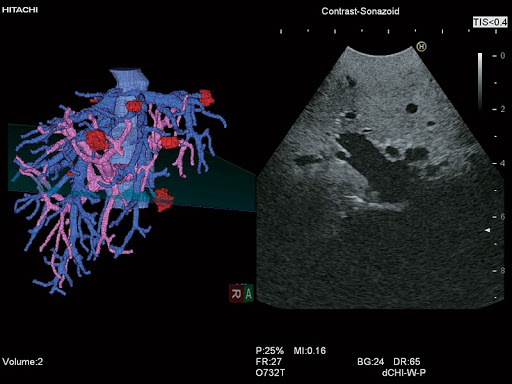

3D и 4D изображения